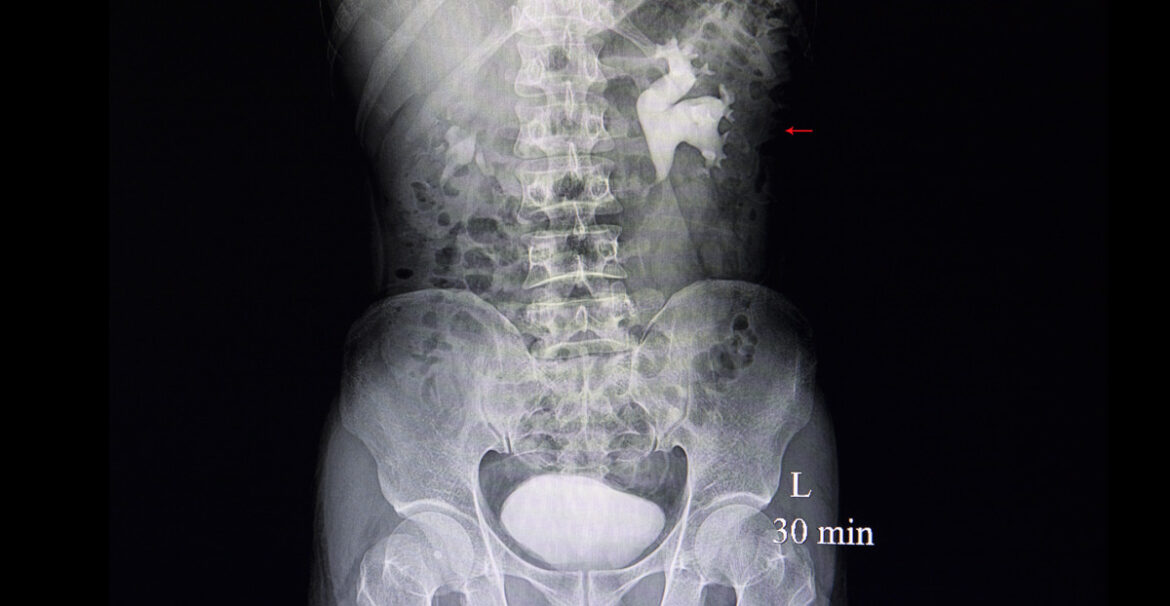

Bilateral hydroureters and hydronephrosis in a neonate ADC Education Hydronephrosis Kidney Baby It occurs in the area where urine collects,. hydronephrosis is a condition, affecting about 1 in 100 babies, where urine overfills or backs up into the kidney, causing the. Most cases resolve without treatment; hydronephrosis is kidney swelling due to urine buildup, often found in prenatal ultrasounds. prenatal hydronephrosis causes kidney swelling in unborn babies. There are. Hydronephrosis Kidney Baby.